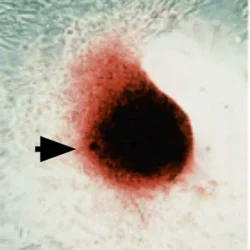

We have shown that, in culture, vascular cells isolated from the aortic media aggregate into nodules (spheroids, arrow) and produce hydroxyapatite mineral.

Spontaneous Calcific Nodule Formation

We have discovered that calcifying vascular cell aggregation into nodules/spheroids (arrow) is enhanced by transforming growth factor-beta (TGF-b) as well as by tumor necrosis factor-alpha (TNF-a).